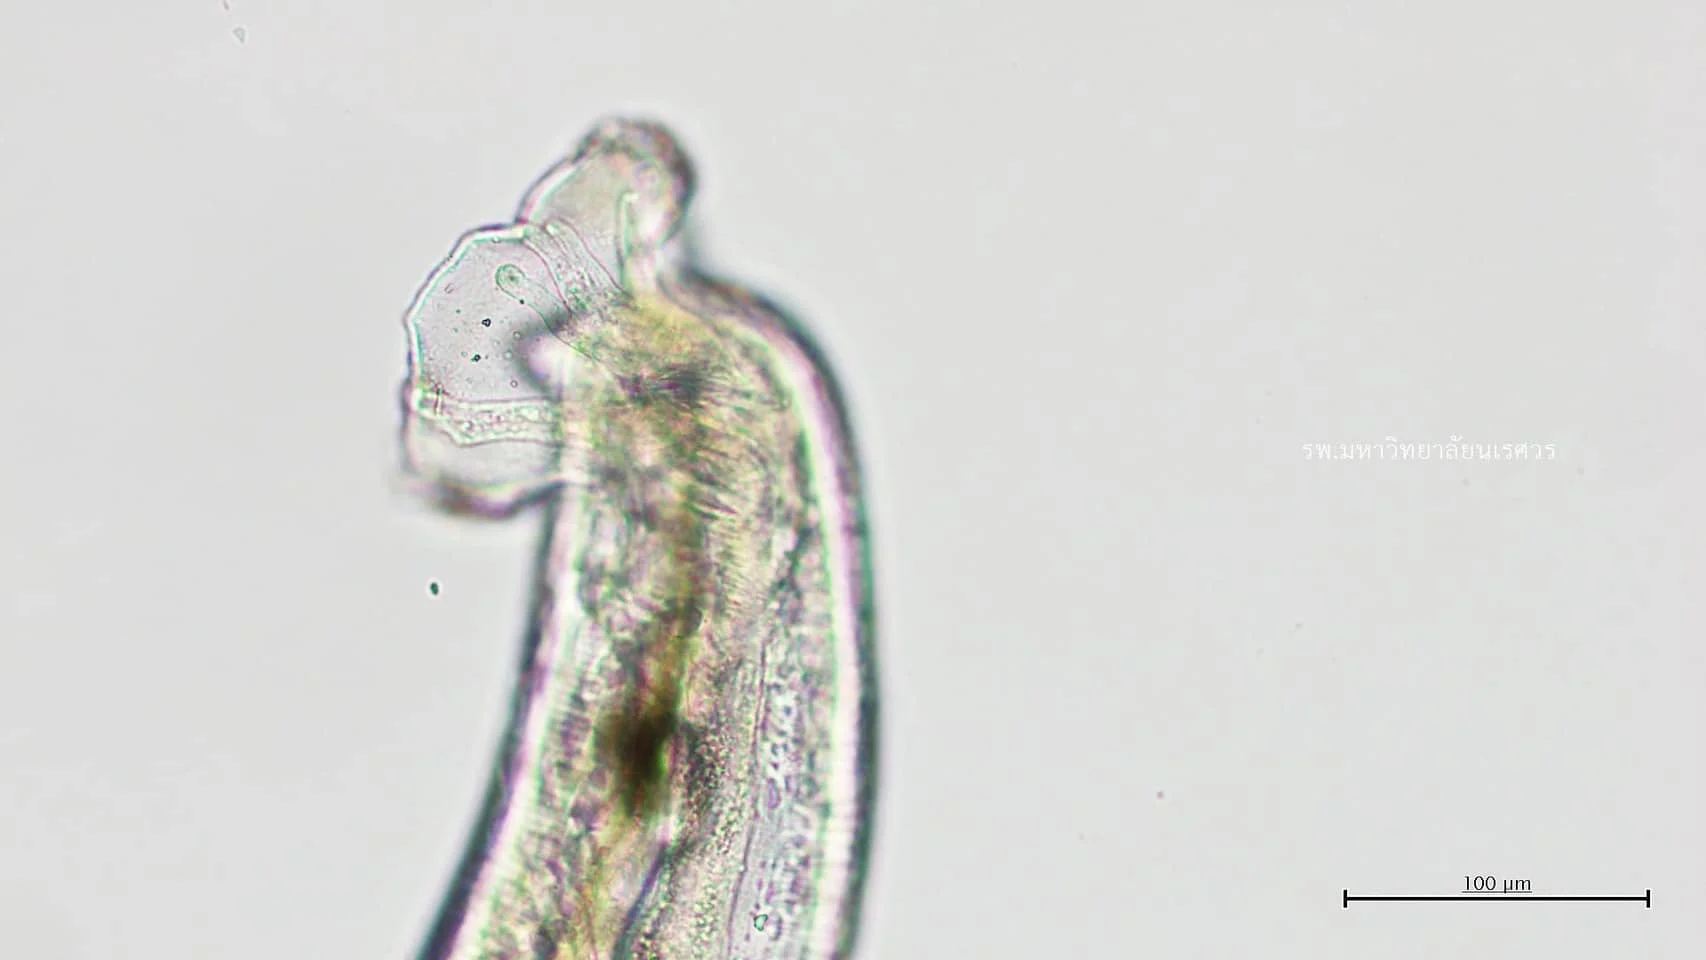

นพ.คณินท์ กล่าวว่า หลังจากได้รับเคสผู้ป่วยมาพบว่าตาคนไข้มีการอักเสบและพบพยาธิในน้ำวุ้นตา จึงรักษาด้วยการให้ยาฆ่าพยาธิและยาลดอักเสบ จากนั้นได้ผ่าตัดโดยใช้เวลาประมาณ 1 ชั่วโมง จึงสามารถนำตัวพยาธิออกมาจากตาได้ ส่งตรวจพบว่าพยาธิที่พบ เป็นพยาธิปอดหนู ความยาวประมาณ 0.5 ซม.

สาเหตุที่เรียกว่าพยาธิปอดหนูเพราะ พยาธิตัวเต็มวัยทั้งสองเพศ จะอาศัยอยู่ในหลอดเลือดแดงของปอดหนู พยาธิตัวเมียจะออกไข่ในหลอดเลือดแดงและฟักตัวเป็นตัวอ่อน ระยะที่ 1 ปนออกมากับมูลหนู เมื่อตัวอ่อนไชเข้าหอยทาก หรือหอยน้ำจืด เช่น หอยโข่ง หอยขม หอยเชอรี่ กุ้งน้ำจืด ปลาน้ำจืด แล้วจะเจริญเป็นตัวอ่อนระยะติดต่อ

ในระยะนี้หากคนรับประทานอาหารปรุงสุกๆ ดิบ พยาธิจะเข้าสู่ระบบประสาท เช่น สมอง ไขสันหลัง หรือตา ฯลฯ อาการเจ็บป่วยจะขึ้นอยู่กับตำแหน่งของอวัยวะที่พยาธิอยู่ เช่น เคสของคนไข้รายนี้ที่ตัวพยาธิขึ้นตาจึงทำให้เกิดอาการที่พบบ่อยคือตามัวลงแบบเฉียบพลัน ไม่มีอาการปวด หรือเคืองตาแต่อย่างใดใด ซึ่งจากการซักประวัติของผู้ป่วยพบว่ามีประวัติชอบทานอาหารสุกๆ ดิบๆ บ่อยครั้ง โดยเฉพาะกุ้งน้ำจืด ที่ทานในเมนูกุ้งแช่น้ำปลาเป็นประจำ